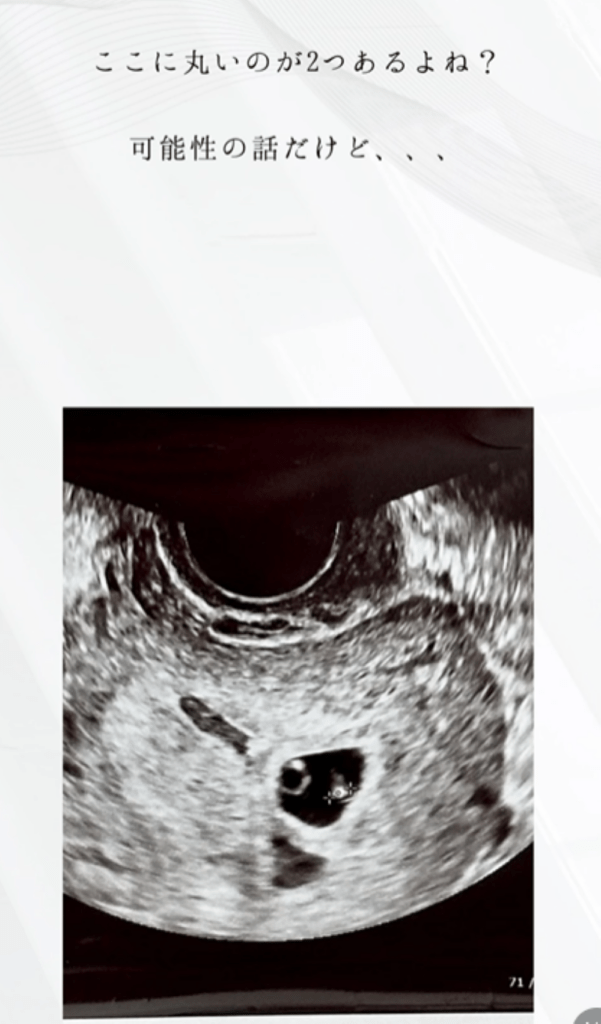

エコー写真と妊婦健診の様子③(@moontwins.0810さんより提供)